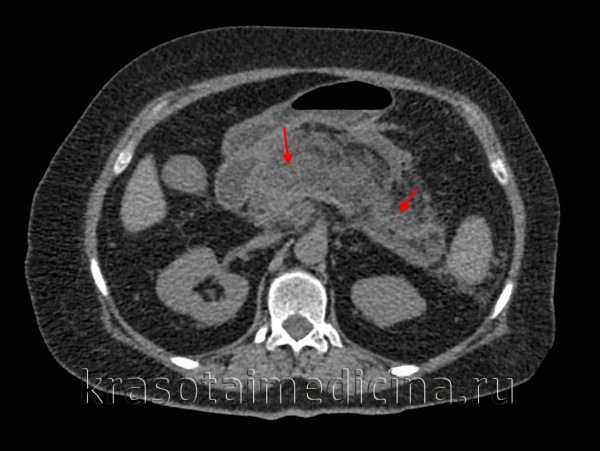

КТ органов брюшной полости. Панкреатит (в области хвоста поджелудочной железы) с наличием отека ее паренхимы, жидкостного содержимого вблизи ее края, на фоне утолщение фасции Героты слева